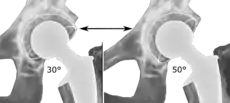

The direction of the acetabular cup influences the range of motion of the leg, and also affects the risk of dislocation.[9] For this purpose, the acetabular inclination and the acetabular anteversion are measurements of cup angulation in the coronal plane and the sagittal plane, respectively.

Acetabular anteversion is normally between 5 and 25°.[9] An anteversion below or above this range increases the risk of dislocation.[9] There is an intra-individual variability in this method because the pelvis may be tilted in various degrees in relation to the transverse plane.[9]